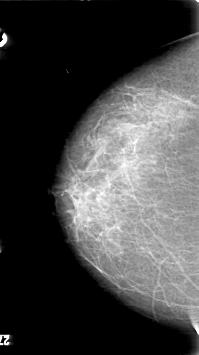

D_4033_1.RIGHT_CC

RIGHT_CC LINES 5311 PIXELS_PER_LINE 2971 BITS_PER_PIXEL 12 RESOLUTION 43.5 NON_OVERLAY